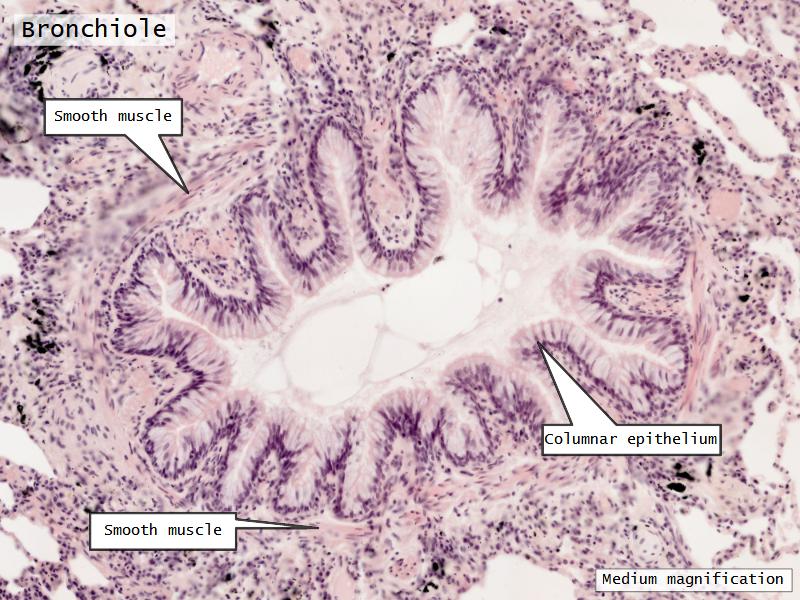

- Bronchioles

- Smooth muscle REPLACE cartilage

- Ciliated columnar > Ciliated cuboidal

- NO glands - goblet cells -> secretory cells